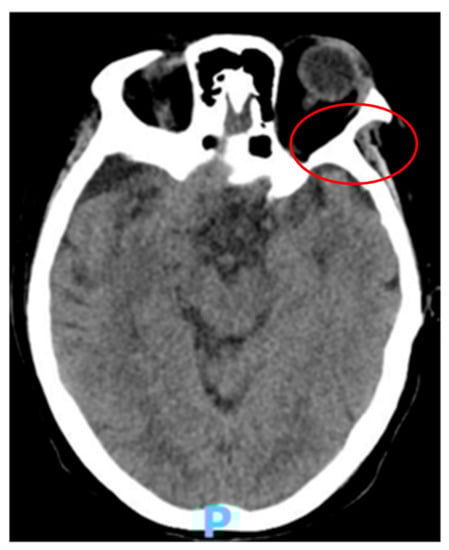

2. Case Presentation